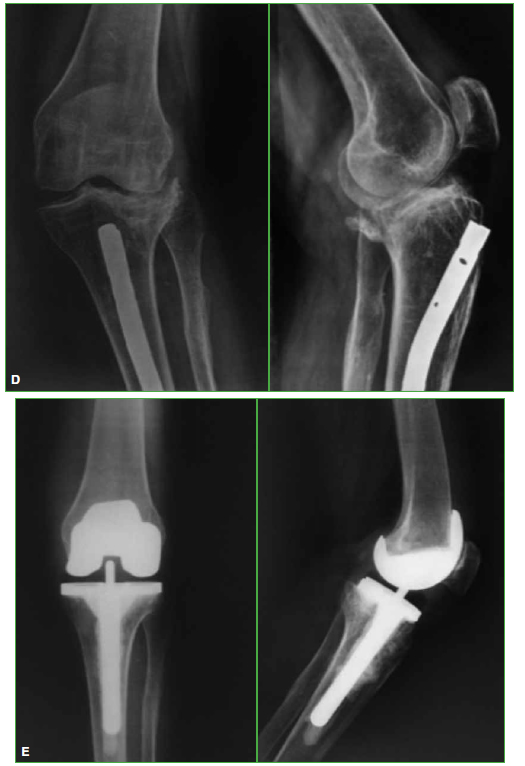

Materiales y Métodos: Estudio retrospectivo observacional, entre mayo de 1999 y enero de 2013. Se evaluaron 25 RTR en 24 pacientes (edad promedio 67.1 años) con secuela de fractura articular de rodilla y un seguimiento promedio de 6.1 años. Tres (12%) tenían cirugías anteriores al RTR. Ocho se resolvieron en dos tiempos. Se empleó un implante constreñido en 4 pacientes (16%). Se determinaron el KSS, el KSSf y el rango de movilidad preoperatorios y del último control. Se documentó la supervivencia del implante.

Resultados: El KSS se incrementó de 38,5 en el preoperatorio a 82,8 en promedio. El KSSf posoperatorio mejoró de 48 a 85. El rango de movilidad aumentó de un promedio de 7,5-76° a 1-102,4° en el posoperatorio. Cuatro casos fueron reoperados. La supervivencia de la prótesis fue del 92% a los 6.1 años.

Conclusiones: El RTR es adecuado para la gonartrosis postraumática en su estadio final, con buenos resultados a mediano plazo. Si se logran una adecuada alineación posoperatoria y un correcto posicionamiento de los componentes, los resultados son satisfactorios y se asemejan a los del RTR por gonartrosis idiopática.